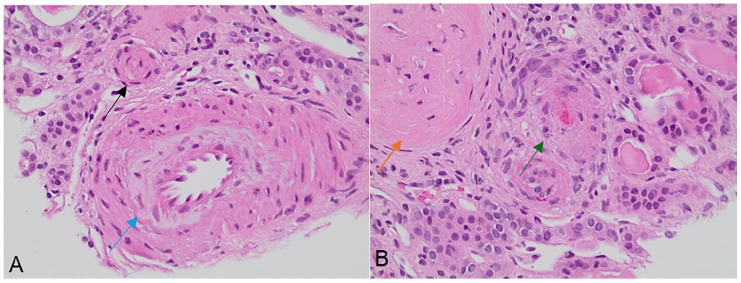

Thrombotic microangiopathy (TMA) is a severe condition characterized by microangiopathic hemolytic anemia, thrombocytopenia, and end-organ damage, often involving the kidneys. Complement-mediated hemolytic uremic syndrome (cHUS), a rare form of TMA, arises from dysregulated alternative complement pathway activation, frequently due to genetic mutations. We report the case of a 23-year-old male presenting with TMA secondary to a heterozygous mutation in the membrane cofactor protein (MCP/CD46) gene. The patient exhibited severe renal and cardiovascular complications, including acute kidney injury requiring hemodialysis, uremic pericarditis, and persistent anemia. Diagnostic evaluation confirmed complement dysregulation, and management with eculizumab, plasmapheresis, and hemodialysis was initiated. Renal biopsy revealed classic TMA features, and genetic testing identified the MCP mutation, underscoring the importance of genetic predispositions in guiding diagnosis and therapy. This case emphasizes the critical role of genetic testing in TMA evaluation and highlights the potential for improved outcomes through targeted complement inhibition and individualized care strategies.